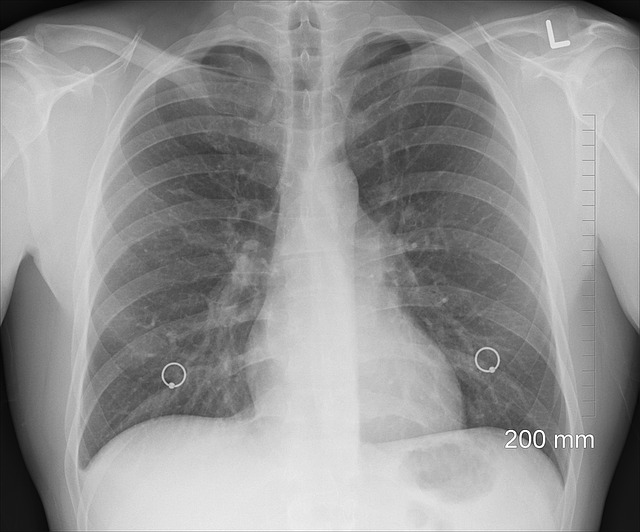

Se conoce como edema pulmonar a la acumulación anormal de líquido dentro de los pulmones. Esta acumulación de líquido, principalmente entre los capilares sanguíneos y los alveolos, es visible porque se aprecia cierta hinchazón en la zona pulmonar.